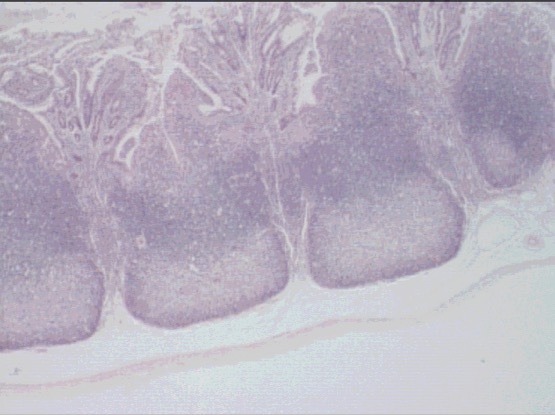

ileum

peyer’s patch

peyers patch

active B lymphs

proliferative (germinal) center

secondary lymphoid nodules